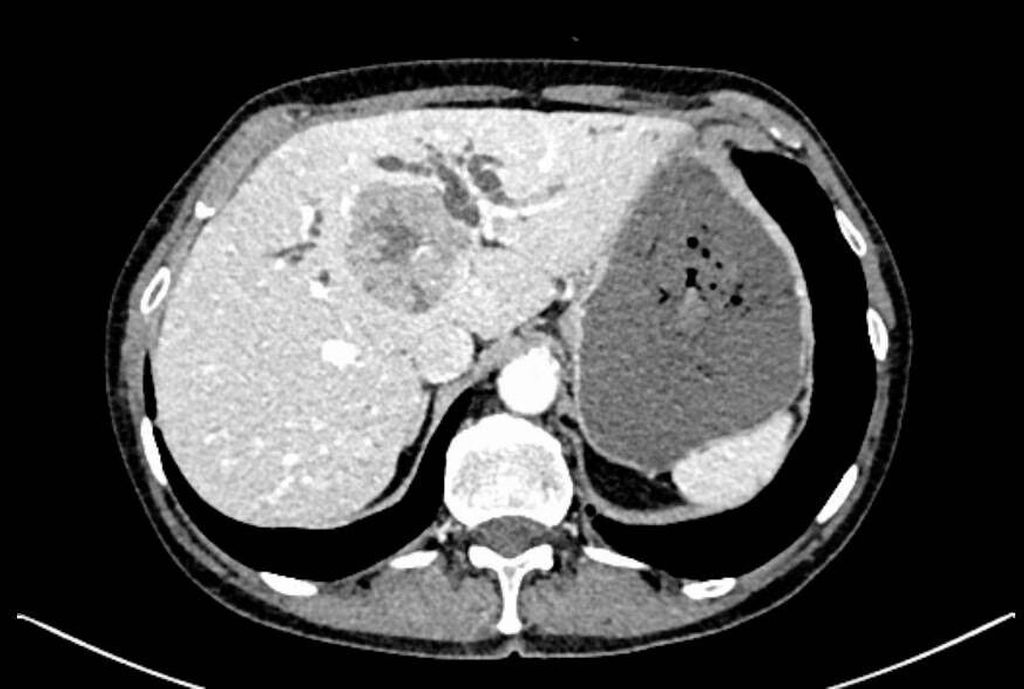

Die initiale CT zeigte eine bis zu 6cm große Raumforderung, ausgehend von der Hepatikusgabel, mit zentraler Infiltration des Leberparenchyms, suspekten Lymphknoten im Leberhilus und retroperitoneal, deutlich dilatierten intrahepatischen Gallengängen sowie Umscheidung und Infiltration des linken Pfortaderastes, jedoch ohne Thrombose. Der Befund war hochverdächtig auf einen cholangiozellulären Tumor. Die histologische Aufarbeitung einer Punktionsbiopsie ergab jedoch ein gering differenziertes, hiläres hepatozelluläres Karzinom (WHO 2019: G3). Angesichts des bildgebenden Befundes und des ebenfalls erhöhten Ca19-9 stand der Verdacht auf einen Mischtumor im Raum.

Bildgebend können sich Mischtumoren wie ein HCC-iCCA-Gemisch imponierend darstellen, wie ein typisches HCC oder aber ein typisches iCCA aussehen oder sich unspezifisch darstellen. Bildgebende Hinweise auf Mischtumoren bestehen bei verschiedenartigem Kontrastmittelverhalten innerhalb eines Tumors (im Verlauf zunehmende Anreicherung, Anreicherung mit Wash-out, Anreicherung ohne Wash-out oder Hypovaskularisierung), vaskulärer Invasion und Gallengangsbeziehungen. Die Kombination erhöhter Tumormarker (AFP und Ca19-9) kann einen Hinweis liefern, ist aber nicht beweisend.